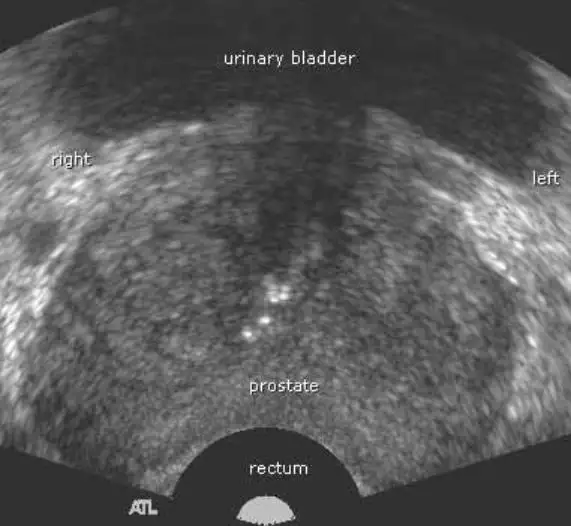

Voiko eturauhassyöpä näkyä ultraäänessä? Kattava opas diagnostiikkaan ja tutkimusmenetelmiin

Voiko eturauhassyöpä näkyä ultraäänessä? Tämä on yksi yleisimmistä…